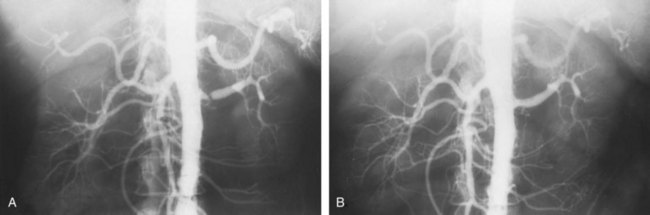

Angiographically, medial fibroplasia demonstrates a typical “string of beads” appearance involving the distal two thirds of the main renal artery and branches (Fig. 39–4). The areas of stenosis are often overshadowed by contrast medium in the microaneurysms, making the degree of actual stenosis difficult to assess. The aneurysms themselves are greater in diameter than the normal renal artery proximal to the disease, and extreme collateral circulation is absent. These are important features in differentiating the lesion from perimedial fibroplasia. Schreiber and colleagues (1984) studied the natural history of renal artery disease due to medial fibroplasia in 66 patients who were followed with serial angiography. Progressive renal artery stenosis (RAS) occurred in 22 patients (33%), and, contrary to an earlier report, this occurrence was no different whether patients were older or younger than 40 years. Significantly, there were no cases of progression to total arterial occlusion in this group. Also, clinical follow-up revealed that serial decreases in either overall renal function or the size of the involved kidney seldom occurred in patients with progressive medial fibroplasia, suggesting that the risk of losing renal function is relatively small in patients with this disease who are managed medically.

Figure 39–4 Selective right renal arteriogram reveals medial fibroplasia involving the main renal artery with typical “string of beads” appearance.

(From Novick AC. Renal vascular hypertension in children. In: Kelalis PP, King LR, Belman AB, editors. Clinical pediatric urology. Philadelphia: WB Saunders; 1984.)

The arteriogram in perimedial fibroplasia may give the appearance of arterial beading, but careful observation shows that the caliber of the normal segment of the vessel is not exceeded by the “bead” (Fig. 39–6). This fact, along with the frequent occurrence of extensive collateral circulation, differentiates this lesion angiographically from that of medial fibroplasia. Perimedial fibroplasia produces severe stenosis, and, although complicating thrombosis or dissection is relatively uncommon, progressive obstruction with ischemic renal atrophy occurs in almost all patients managed nonoperatively.

Figure 39–6 Renal arteriogram in a patient with perimedial fibroplasia shows slightly irregular, yet severe, stenosis of the midrenal artery (arrows) associated with extensive collateral circulation to the kidney. The small size of the arterial irregularities and the presence of collateral circulation distinguishes this lesion radiographically from medial fibroplasia.